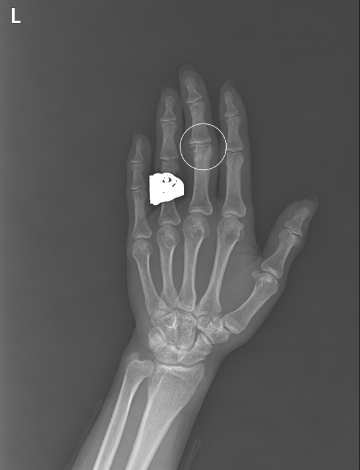

수술전

2020.07.14

수술후

2022.01.07